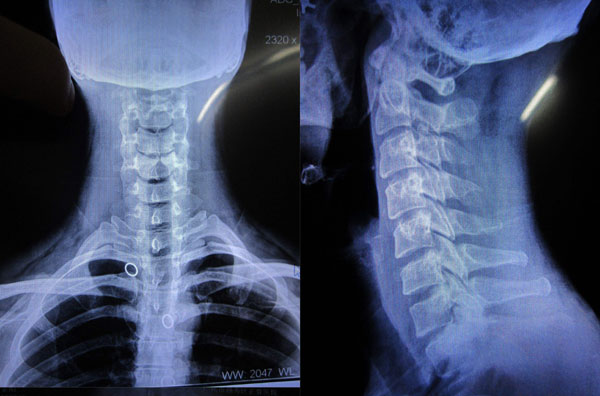

那么,孕期拍X光片或者CT检查真的会影响胎儿发育吗?需要做流产吗?

大量研究已经证明:X射线对包括人类在内的所有哺乳动物和幼崽,甚至胚胎所产生的的不良影响都存在一个阈[yù]值的。简单的说:并不是只要接触了辐射就对人体产生危害,无论是成年人还是胎儿,接受到的辐射只有达到一定程度时才会有损伤。

美国妇产科协会(ACOG)在2017年曾经发布过相关的指南,X射线辐射对胎儿的影响和风险,主要取决于胎龄和射线剂量两个因素。不同胎龄有各自对应的射线安全剂量。

(1)妊娠0-2周,导致畸形的剂量阈值是20mSV-100mSV,主要影响是导致胎儿死亡。

(2)妊娠2-8周,导致畸形的剂量阈值是200mSV,主要影响是导致胎儿先天畸形。

(3)妊娠8-15周,导致畸形的剂量阈值是60mSV-310mSV,主要会影响智力和导致畸形。

(4)妊娠16-25周,导致畸形的剂量阈值是250mSV-280mSV,主要影响的是智力。

由此可以判断,在所有胎龄里,最小的剂量阈值是50mSV,就是说,只要射线的剂量没有超过这个数值就不会对胎儿有影响。

医院里的X光和CT射线量有多少呢?

一张普通的胸片:0.02mSV;

一张膝关节X线:0.005mSV;

一张普通牙片:0.01mSV;

一个头部CT:2mSV;

一个胸部CT:8mSV。

所有这些检查的辐射剂量远远低于最小的阈值50mSV。

连着拍2500次胸片或者连着做6次胸部CT才有可能达到最小的阈值。此外,医院里彩超和磁共振这些检查更是安全的,对胎儿没有影响。

所以,怀孕期间接收X线检查,完全没有必要紧张,更没有必要做流产。拍了X光片后短期内不能要孩子更是谣传。但是,妊娠期间不能使用放射性碘同位素做治疗。